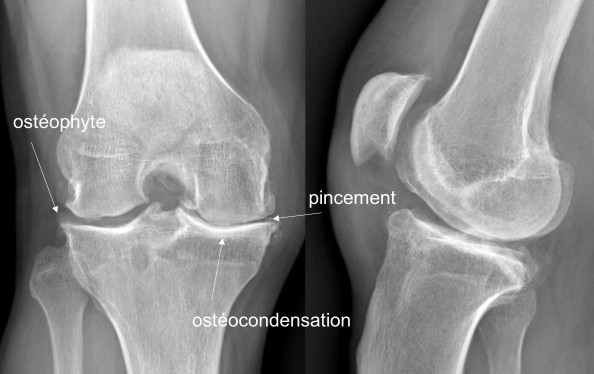

La prothèse de genou est constituée d’implants permettant le remplacement de l’articulation usée.